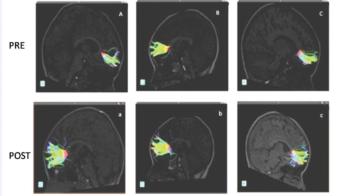

The study participants underwent pre- and post-musical-training evaluation with diffusion tensor imaging (DTI) of the brain. DTI is an advanced MRI technique, which identifies microstructural changes in the brain's white matter.

The brain's white matter is composed of millions of nerve fibers called axons that act like communication cables connecting various regions of the brain. Diffusion tensor imaging produces a measurement, called fractional anisotropy (FA), of the movement of extracellular water molecules along axons. In healthy white matter, the direction of extracellular water molecules is fairly uniform and measures high in fractional anisotropy. When water movement is more random, FA values decrease, suggesting abnormalities.

After the children in the study completed nine months of musical instruction using Boomwhackers—percussion tubes cut to the exact length to create pitches in a diatonic scale, DTI results showed an increase in FA and axon fiber length in different areas of the brain, most notably in the minor forceps.

Images (JPG, TIF):